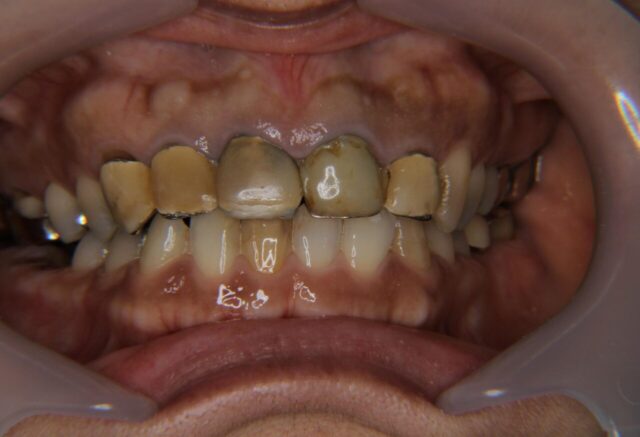

歯周外科処置を含む前歯セラミック治療と臼歯インプラント治療

Before

| 主訴 | さし歯が取れた |

| 年齢 | 40代 |

| 性別 | 女性 |

| 治療期間・回数 | 5ヶ月、14回 |

| 治療方法 | 歯周治療、歯周外科手術、セラミック治療、インプラント治療 |

| 費用 | 1,090,800円 |

| デメリット・注意点 | セラミックとインプラントの費用で保険診療分は含まず |

| 備考 | 前歯は5本、e-maxセラミックを使用。 臼歯インプラントは2本、ジルコニアセラミックを使用。 表示されている費用は当時の価格となっています。 前歯を美しく仕上げるため、歯周治療と歯周外科手術を丁寧に行いました。 セラミックは白くて当たり前ですが、歯ぐきとの調和を重視して治療しました。 |